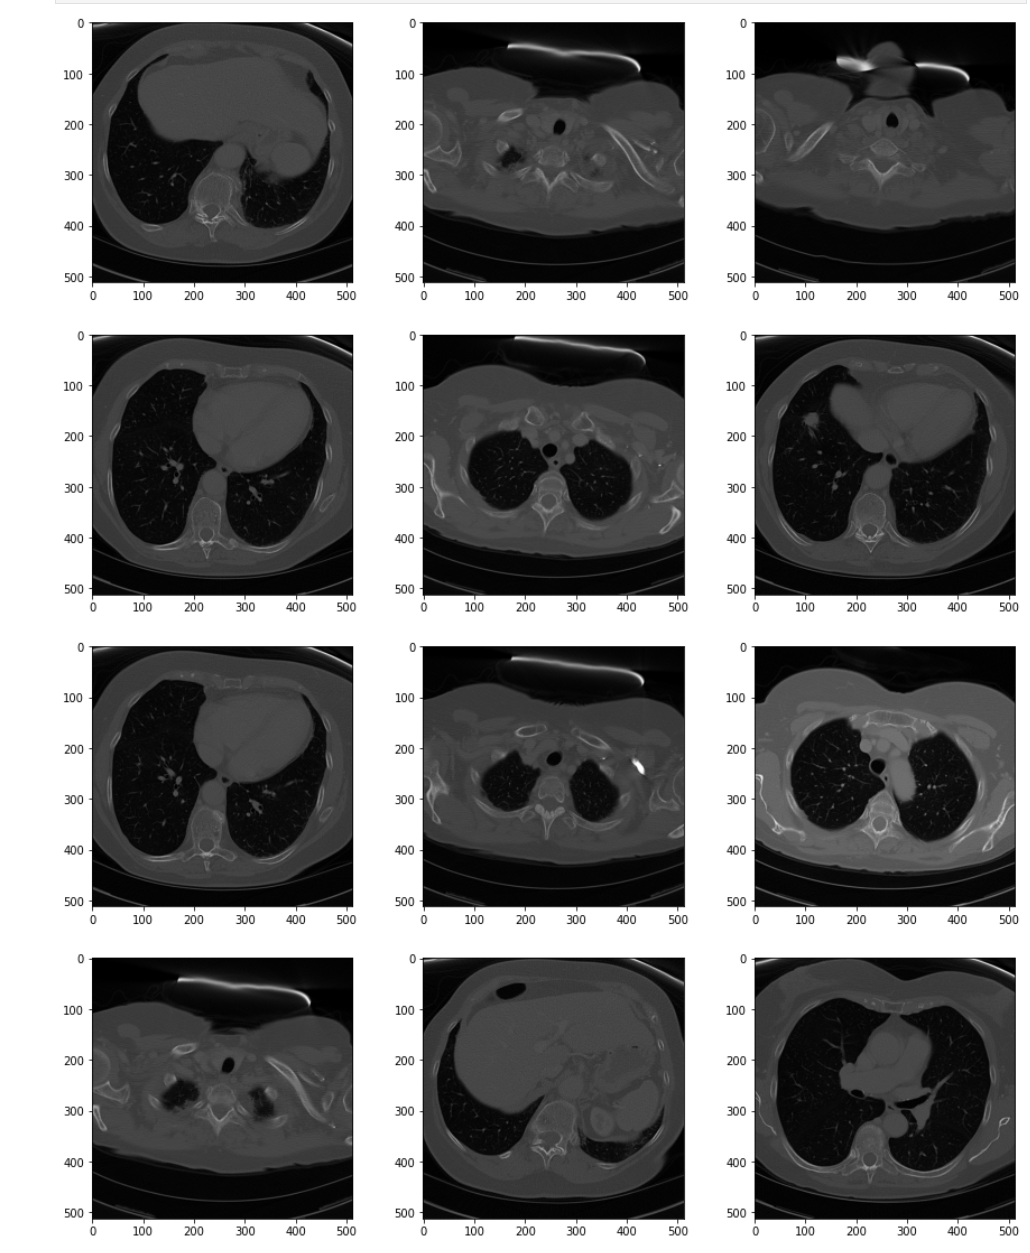

Image Series

The single image represents a pretty standard, unprocessed scan. It was selected more or less at random from the stack and happens to come from about mid-level in the chest. While completely adequate, it could be enhanced before being passed to a radiologist for reading or to a machine learning algorithm for segmentation. One common enhancement is to improve the contrast between different tissue types, such as bone and muscle. While some distinction between the tissues is visible in this image, it is subtle.

Before performing such processing, however, it is important to make sure that the images in the series are uniform. While CT is a pretty consistent imaging modality, it is not uncommon to get differences in pixel intensity between the layers. The quickest way to make such determinations is to sample the images in the scan and generate a panel plot with many images side-by-side.

The code in the listing below creates a helper method to manage visualization of the series. It takes a NumPy array with the data series and outputs a panel plot with a specified number of rows and columns.

- Because we only want to visualize part of the series, the method includes a parameter to control the size of the step:

sstep

. It also provides a second parameter to control the number of columns the panel image should have:fcols

. - From the panel and the size of the image series, the number of rows is calculated as

frows

. If you haven't seen it before,//

is the operator for integer division in Python 3. - The individual panels in the diagram are created using the

matplotlib.pyplot.subplot

method. Each iteration through the sequence moves the figure to the next panel in the sequence. - The image is displayed using

imshow

, again utilizing the grayscale color map.

# Helper method to generate panel series of CT image data def display_series(idata, sstep=5, fcols=3, cmap=plt.cm.gray): ''' Create a sample panel to inspect the provided series as a whole. Samples images from the sequence based on the provided step. @input sstep (int, default=5): Number of images to skip when creating the series panel graphic. @input fcols (int, default=3): Number of columns to display in the panel graphic. ''' frows = idata.shape[0]//sstep//fcols + 1 for i,idx in enumerate(range(0, idata.shape[0], sstep)): sub = plt.pyplot.subplot(frows, fcols, i+1) sub.imshow(idata[idx,:,:], cmap=cmap)

Next we use the method to visualize the raw data.

# Create a sample panel to inspect the series as a whole plt.pyplot.figure(figsize=(15,35)) display_series(ct_idata)

The series as a whole has "poor contrast." Pixel values are dark and the relative difference between types of tissue is small. The general pixel distribution between the slices, however, is consistent. This is a good candidate to enhance by increasing the contrast.